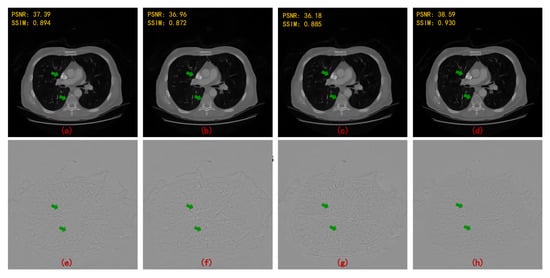

| 90 Views | 60 Views | |||

|---|---|---|---|---|

| PSNR | SSIM | PSNR | SSIM | |

| FBPConvNet [13] | 37.611 | 0.921 | 35.578 | 0.896 |

| RED-CNN [14] | 37.209 | 0.902 | 34.528 | 0.859 |

| DD-Net [22] | 36.380 | 0.912 | 34.424 | 0.892 |

| MWCNN [23] | 38.664 | 0.943 | 36.531 | 0.921 |

| HDNet (WCNN-based) [29] | 34.506 | 0.900 | 32.259 | 0.869 |

| HDNet (Unet-based) [30] | 35.459 | 0.903 | 33.377 | 0.886 |

| HDNet (WUnet-based) | 36.750 | 0.924 | 35.132 | 0.904 |

| HDNet (MWCNN-based) | 40.204 | 0.956 | 37.718 | 0.938 |